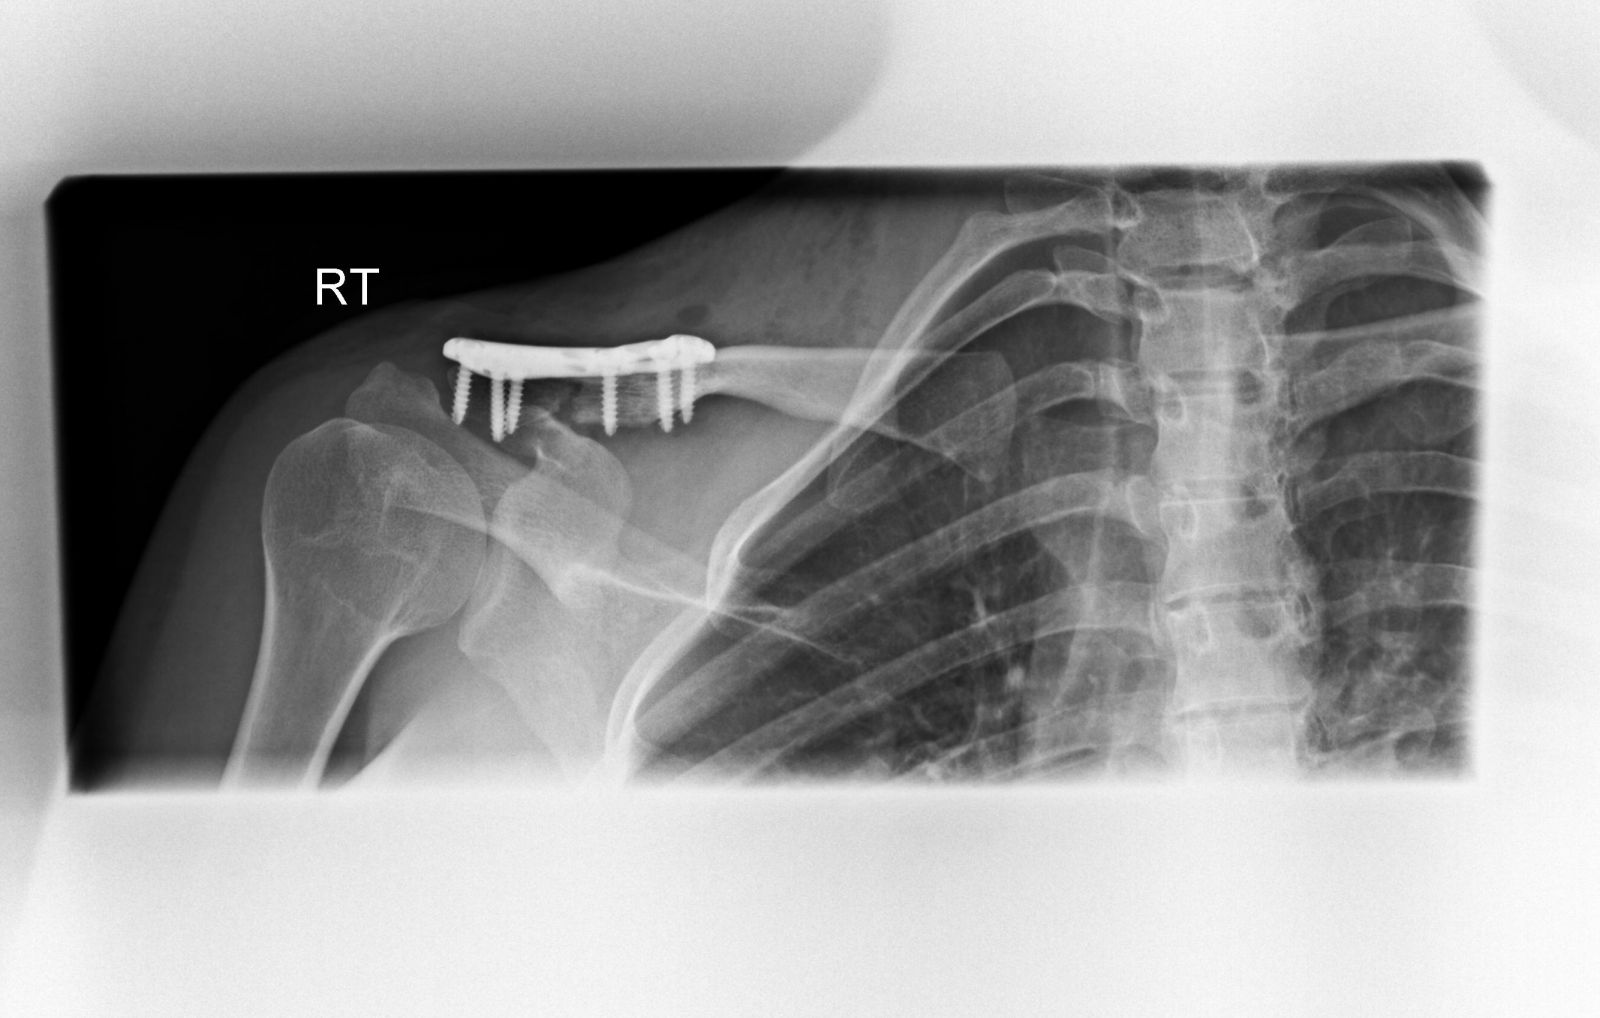

Η οστεοσύνθεση γίνεται κυρίως με χρήση πλάκας και βιδών (κοχλίες). Η πλάκα διαθέτει οπές (τρύπες), μέσα από τις οποίες εισάγουμε τις βίδες στα διάφορα τμήματα της κλείδας και τα συγκρατούμε στην ανατομική τους θέση. Η κατασκευή πλάκα-βίδες-κλείδα είναι πολύ σταθερή και επιτρέπει την πώρωση του κατάγματος σε λίγες εβδομάδες.

Μετεγχειρητικά, οστεοσύνθεση κατάγματος και αποκατάσταση κορακοκλειδικών συνδέσμων